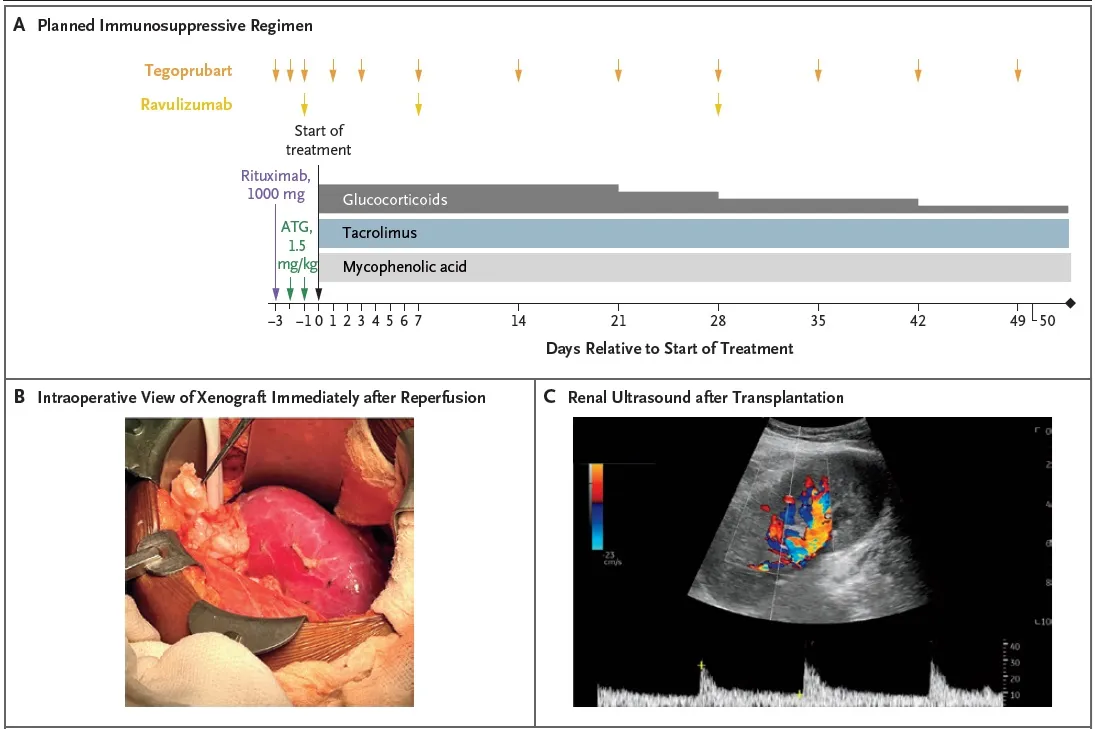

Confere o esquema de imunossupressão utilizado, bem como achados do intraoperatório:

Indução

* Timoglobulina (ATG) 1,5 mg/kg

* Rituximabe (1000 mg)

* Tegoprubart (anti-CD154, bloqueia a produção de anticorpos)

* Ravalizumabe (anti-C5)

Manutenção

* Prednisona, tacrolimo e micofenolato